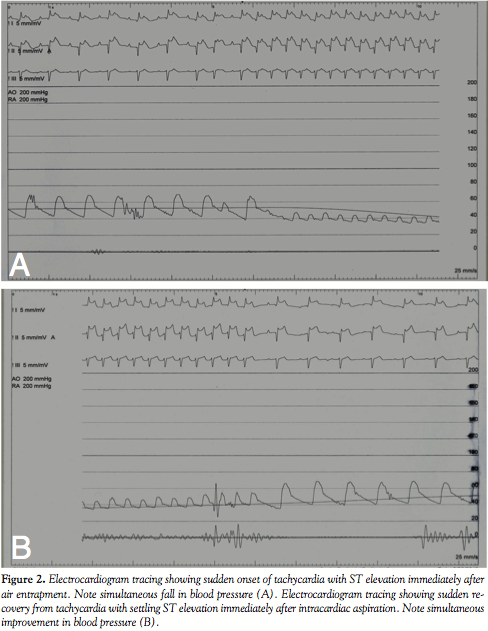

Under general anesthesia, vascular access was obtained from the right femoral vein and artery. The Swan-Ganz balloon flotation catheter was introduced into the right atrium. As soon as the catheter was inflated with room air, it burst and an air pocket was seen within the right ventricle (Figure 1; Video 1) resulting in “air lock,” or venous air embolism. Within fractions of a second the patient’s blood pressure started falling and arterial saturation dropped to 50%. The cardiac monitor showed sinus tachycardia with gross ST segment elevation and hypotension (mean blood pressure 36mm Hg; Figure 2A). Immediately, we started high flow oxygen and we planned to aspirate the air. A 6 Fr angiographic catheter (Berman) was introduced into the right ventricle and directed toward the air pocket, and manual aspiration (Video 2) was initiated. During the process of aspiration, a few smaller bubbles embolized into the pulmonary and systemic circulation (via large nonrestrictive VSD and overriding aorta), however we aspirated the majority of the air. As soon as the air was aspirated blood pressure dramatically improved, tachycardia improved, and ST elevation settled (Figure 2B).